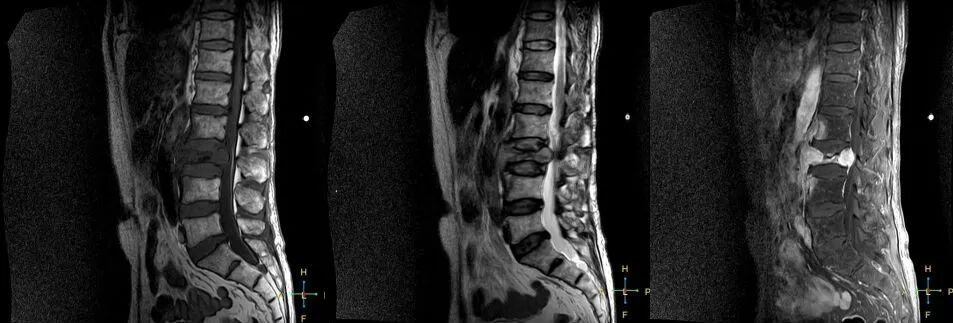

2 良性压缩性骨折 椎体形态:楔形、凹陷形。 椎体连续性病变(骨质疏松):新鲜、陈旧骨折并存。

椎间盘改变:椎间盘增厚呈双凸透镜状, 椎间盘疝入椎体, 形成许莫氏结节。

椎体后上角或后下角向后翘起, 呈尖突样突入椎管, 具有特异性,为其它原因的骨折所少见。

——良性压缩性骨折MR信号特点—— 良性骨折的修复过程:缺血性变化--修复(骨髓水肿、血流增加或充血现象)--修复近完成(血流恢复正常)--慢性期(脂肪组织再生)。 正常成人:椎体为黄骨髓,T1WI 、T2WI 均为高信号。 当骨髓内出现水肿时,T1 低信号, 与残余的正常骨髓形成明显对比,所以椎体压缩骨折后,MR 信号改变以 T1WI 上观察最好;而在常规 T2WI 图像上,病变骨髓的长 T2 高信号与正常骨髓脂肪信号差别较小,不易观察;T2WI 脂肪抑制技术对于突出显示骨折区长 T2 组织信号具有独特优势,对于判断椎体是否发生脂肪变及骨折是否愈合也有一定价值。 急性早期,椎体压缩,局部缺血,骨髓水肿,T1WI 不均匀低信号,T2WI 高信号,增强扫描无明显的强化。 随后,骨折部位开始修复,血流量增加,增强扫描可出现明显的强化,平扫信号无改变。 慢性期,骨髓内脂肪组织再生,T1WI 椎体内呈混杂高信号。

由于大多数外力轻微,椎体内多形成范围局限、移位不明显的骨折线,骨折线周围水肿亦多局限,因此,较少出现全椎体信号异常。

椎体后角回避现象:T1WI 椎体上部或大部呈低信号, 而后角信号不变。

椎弓根改变:由于旋转的扭力或是上下的压力造成椎体血流循环改变而致椎弓根的髓内水肿,使信号改变累及椎弓根,但椎弓根无变形或膨大。

所以,椎弓根的信号改变并非恶性骨肿瘤所特有,约20%~ 30%的良性压缩性骨折会出现椎弓根水肿而信号增高。 恶性压缩性骨折, 约有60%~ 80%出现椎弓根水肿及信号变化,而在椎弓根出现不正常信号的恶性压缩性骨折中, 约有50%~70%出现椎弓根膨大的现象,为其特异性, 可作为鉴别诊断的依据。 椎旁软组织肿块:最典型的表现为椎旁一薄环状异常信号带,因为椎体压缩时常继发椎旁软组织水肿与出血, 这一征象多见于单纯骨折, 病理性骨折少见。

3 恶性压缩性骨折 椎体上下径变窄而前后径增大,椎体后部皮质后突,后角一般表现圆钝,无上翘,常呈球形突出,致椎管狭窄,即膨胀性盘状破坏,硬膜囊和脊髓受压。

——恶性压缩性骨折MR信号特点—— 由于肿瘤组织的侵犯,T1WI上椎体呈弥漫性低信号,T2WI呈高信号,增强扫描呈明显不均匀强化。

4 总结:鉴别诊断 ——良性压缩性骨折—— 楔形或凹陷形 连续性分布 椎间盘增厚双凸状,许莫氏结节 急性期T1WI不均匀低信号 椎体后角翘起突入椎管内 椎体后角回避现象 可伴椎弓根水肿、无膨大 椎旁薄环形软组织影

——恶性压缩性骨折—— 扁平形或倒楔形 跳跃性分布(转移瘤) 椎间盘不受累 T1WI均匀低信号 后角圆钝,膨胀性盘状破坏 椎弓根受累、膨大 椎旁分叶状及肿瘤样软组织肿块